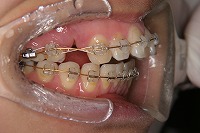

右

23歳5か月